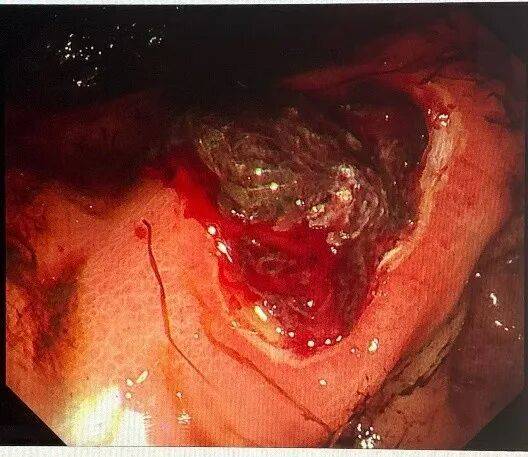

一位68岁中老年女性患者,主因“间断上腹部绞痛3天”前来就诊,患者自述3天前进食较多山楂等食物后间断出现上腹部绞痛、夜间为甚,无恶心呕吐、无腹泻、无发热;无头晕头痛、无胸闷胸痛,纳少,眠一般,二便可。入院后完善相关检查,胃镜提示:胃底、体粘液池可见大量暗红色内容物,腔内可见一枚大小约8*7cm胃石,另见大量食物残渣,影响观察。质稍软,予以异物钳、圈套器勒扎,石体成若干小块。胃角可见一巨大溃疡,予内镜下处理。